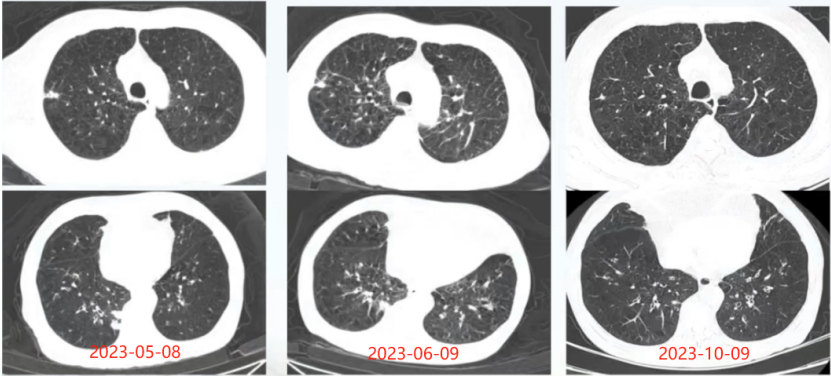

5月8日复查胸部CT可见空洞样病变较前有所吸收; 6月9日复查病灶进一步吸收10月9日随访胸部CT见病灶基本完全吸收(图15)

图片

15  患者病程中胸部CT对比